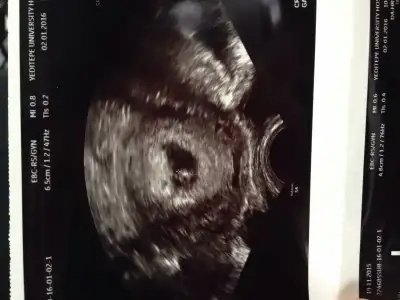

Vajinal bakıldıysa erkek, karından bakıldıysa kız gibi geldi bana canım... Allah gönlüne göre bersşn, hayırlısı olsunnKızlar iyi akşamlar, benim usg görüntüsünü de yorumlar mısınız? LütfenEki Görüntüle 1731814

Benimkine cok benziyor hem kese hemde konumu olarak. Benim oglum oluyor insallah :)Bunuda yorumlayabilirmisiniz rica etsem